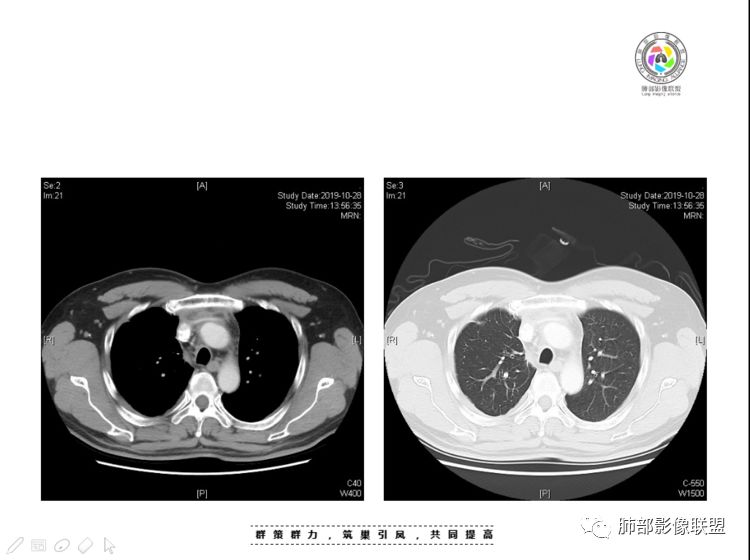

穿越七海的风:右前纵隔占位,恶性肿瘤,生殖来源?右肺实变是占位or肺不张?考虑为部分肺不张FeNo:右前纵隔占位,右肺结节,胸膜凹陷,小尾巴,右肺不张,考虑恶性杨旭华:恶性,前纵隔肿物,与血管关系密切,上腔静脉变窄,右肺野一元论考虑叶间裂增厚,恶性胸膜间皮瘤可能大小丽:到底是纵隔来源还是胸膜来源?我怎么倾向于胸膜来源,和叶间胸膜关系密切,而且纵隔内上腔静脉是向内侧推移。胸膜肿瘤(间皮瘤?SFT?)包裹性胸腔积液?马春平(张家港市一院胸外科):前纵隔占位,左无名受压,右大量胸腔积液可能是胸导管汇入处侵犯受压,考虑纵隔鳞癌孙冰伟:右上纵隔占位,也感觉和叶间胸膜关系密切,右侧胸膜局限性增厚,考虑恶性可能性大灵:前纵隔占位,血性胸水,胸膜凹凸不平,查见肿瘤细胞,结合免疫组化考虑胸腺癌。鉴别胸膜间皮瘤。采莲:右前上纵膈旁可见类圆形肿块,纵隔血管内移,感觉来源于胸膜,肿块内密度低,似水样密度,右侧胸膜广泛增厚,少量胸腔积液。心包少量积液。考虑胸膜间皮瘤,鉴别肺癌并胸膜转移?水晶石头:患者中年男性,胸闷15天。有“高血压、慢性肾小球肾炎”病史。查肿瘤标志物正常,胸水提示渗出液,胸水病理查见瘤细胞。胸部CT:右肺上叶后段结节、斑片影,见胸膜牵拉、包裹积液及部分纤维条索灶,似见卫星灶,右侧胸膜增厚。前纵隔脂肪密度增厚,右侧可见类圆形低密度(液体)肿块,边缘光滑。综合考虑右肺腺癌并胸膜转移,结核可能。周太狼:考虑纵隔胸膜来源肿瘤,恶性,胸膜间皮瘤伴转移?徐飞:中年男性,影像为右侧胸腔及叶间积液,叶间胸膜增厚轻度强化。前纵隔右侧心缘旁团块,可见坏死。胸水见癌细胞,综合考虑恶性,胸腺癌伴转移。小赵:中年男性,血性胸水,常规查见癌细胞,李凡他实验阳性。胸部CT示前纵隔见不均匀密度影,与邻近大血管分界不清,囊变坏死明显,增强扫描呈不均匀强化,心包及右侧胸膜增厚,并心包及右侧胸腔少量积液。综合考虑胸腺癌。右肺中叶病变周围见多发纤维条索,支气管部分进入病灶,考虑炎性病变。流心明智:患者,男性,50岁。胸闷15天。高血压20年,慢性肾小球肾炎15年。肿标正常,胸水提示渗出液,胸水查见癌细胞。胸部CT:右肺肿块影,斑片影,索条影,可见胸膜牵拉、多发包裹积液,纵隔上腔静脉受累,心包受累。综合考虑:ROSE似腺?考虑右肺腺癌并胸膜转移,心包受累。鉴别胸腺Ca、淋巴瘤,纵隔病变不懂,等老师们精彩分析。王秀仙:前纵膈囊实性肿块,与纵膈分界不清,心脏大血管及上腔静脉受压向内后移,右侧后胸膜、侧胸膜增厚,右侧叶间裂不规则增厚,心包积液,根据腔静脉移位情况,考虑纵膈胸膜来源恶性肿瘤,胸膜间皮瘤?鉴别胸腺癌并胸膜转移。高广飞:上纵隔占位,右侧叶间胸腔积液,需考虑恶性自信人生:多发囊实性病灶,包裹性积液,考虑胸膜来源 只是没有看到壁结节,恶性胸膜间皮瘤巴伟:前上纵隔占位,胸膜及心包结节,考虑胸腺瘤或癌,右肺病灶,先考虑陈旧炎性病变。Lenle董:前纵隔占位,部分边缘模糊,病灶内囊变?坏死?上腔静脉受侵,考虑胸腺癌;叶间片状影,强化明显,炎性考虑。常志强:前纵隔囊实混杂密度肿块,边界不清,实性部分强化明显,结合胸水内见癌细胞,考虑恶性肿瘤伴转移。飞鹰行动:前纵隔占位,软组织密度及囊性密度,实性部分密度均匀,致密,病灶与周围血管分界不清,增强后病灶强化有类似不温不火强化,部分血管受侵犯,右肺见肿块样病变及条索状病变,一元论,考虑淋巴瘤,二元论,考虑胸腺瘤B2—B3伴右肺病变。尽量一元论考虑,淋巴瘤可能。看图说话:右肺索条病灶,边缘膨隆,胸膜牵拉,考虑右肺癌伴胸膜转移。晨:前纵隔囊实性肿块,与纵隔分界不清,右侧后胸膜、侧胸膜增厚,右侧叶间裂不规则增厚,考虑纵隔胸膜来源恶性肿瘤,考虑胸腺癌并胸膜转移。丽:中年男性,前纵隔囊实性肿块,呈偏心性生长,临近大血管受压推移,增强后实性部分不均匀强化,心包可见条形积液,考虑胸膜来源恶性肿瘤,胸腺癌可能大。另右肺多发斑片状高密度影及实变密度影,实变影呈均匀强化,右侧胸膜局限性增厚,考虑炎性病变。小飞:右前纵隔囊实性占位,实性部分明显强化,右侧叶间胸膜增厚,右侧胸腔积液,心包积液,考虑恶性胸腺瘤!尘缘:支持恶性胸腺瘤(囊实性肿块,实性强化,且侵犯纵隔,脂肪间隙模糊)伴肺内及胸膜转移。浪迹天涯:考虑侵袭性胸腺瘤——胸腺前纵隔占位,周围脂肪间隙模糊不清。尘缘:不除外另一种可能:二元,肺内腺癌合并胸膜转移,纵隔的畸胎瘤可能。一米阳光:晨读中年男性,右肺结节影,叶间裂及胸膜增厚牵拉,右侧胸水。心包多发结节改变。胸水查见癌细胞。考虑,腺癌并转移。鉴别,胸膜间皮瘤并转移前纵隔囊实性占位,二元考虑。心灵鸡汤:老年男性,右肺中叶外段长条状软组织密度影,边缘膨隆,邻近胸膜牵拉,部分胸膜有栽脏,右中叶外侧段支气管堵塞,常规考虑恶性肿瘤,腺癌可能,结核、鳞癌不除外,另右肺上叶斑片影,小叶性肺不张?右前纵隔囊实性不规则形密度影,其内见部分脂肪样极低密度影,与邻近血管边界不清,心包外膜有侵犯,增强未见纵隔窗平扫,实性及分隔见增化,其内低密度影未强化,考虑低度恶性纵隔肿瘤,间皮瘤可能,畸胎瘤、淋巴瘤待排,建议支气管镜及穿刺活检。曹志勇:右前纵隔考虑来源于胸膜的恶性肿瘤,右肺内病灶考虑鳞癌,二元德芙~云味:中年男性,右肺见结节、斑片影,右侧包裹积液、胸膜牵拉,纤维条索,前纵隔囊性占位,考虑腺癌、并转移。欧阳英:右前中纵隔囊实性肿块及右肺内结节灶,支持恶性肿瘤,胸腺癌并肺内转移可能张延军:前纵隔见不规则软组织影,密度不均,右侧缘见囊变区,纵膈及侧胸壁胸膜增厚,增强呈不均匀强化,右肺中叶见结节灶,近段支气管阻塞,叶间胸膜不规则增厚,考虑1:右肺中叶腺癌伴纵膈及胸膜转移;2:前纵膈侵袭性胸腺瘤并胸膜侵犯,中叶炎性改变?彭君:老年,前纵隔占位 ,坏死边缘清, 侵犯心包 右侧胸膜及叶间胸膜结节 ,少量胸水, cea不高 ,考虑恶性, 间皮瘤可能 ,转移待除外。毛勤香:恶性没问题,胸水查见癌细胞,一元还是2元,右肺中叶肿块,边缘毛糙,局部似有毛刺,周围有粘连,右侧胸膜腔少量积液,胸膜增厚多发结节,含叶间裂结节,纵膈脂肪间隙模糊,纵膈胸膜增厚,心包增厚积液,右前那个类圆形低密度肿块,纵膈血管内移,我考虑胸膜来源可能性大,综合考虑,一元肺腺癌并多发转移,二元考虑胸膜间皮瘤并多发转移,肺内炎症不张。

本例纵隔与肺内两处病变,回顾总结分析:

1、右肺内病灶,病灶呈结节样,边缘欠规则,局部膨隆,叶间裂胸膜牵拉凹陷,再看相应支气管腔堵塞截断,临床资料胸水中查到癌细胞,均提示病灶倾向恶性,腺癌的病理意见与之相吻合。

2、前纵隔内病灶囊实性混杂密度病灶,囊性病灶主要位于右侧,张力较高,有分隔影,囊壁右侧缘光整,病灶左侧实性部分边界不清明显强化,病灶肺瘤交界面大部分边界清楚,部分模糊。